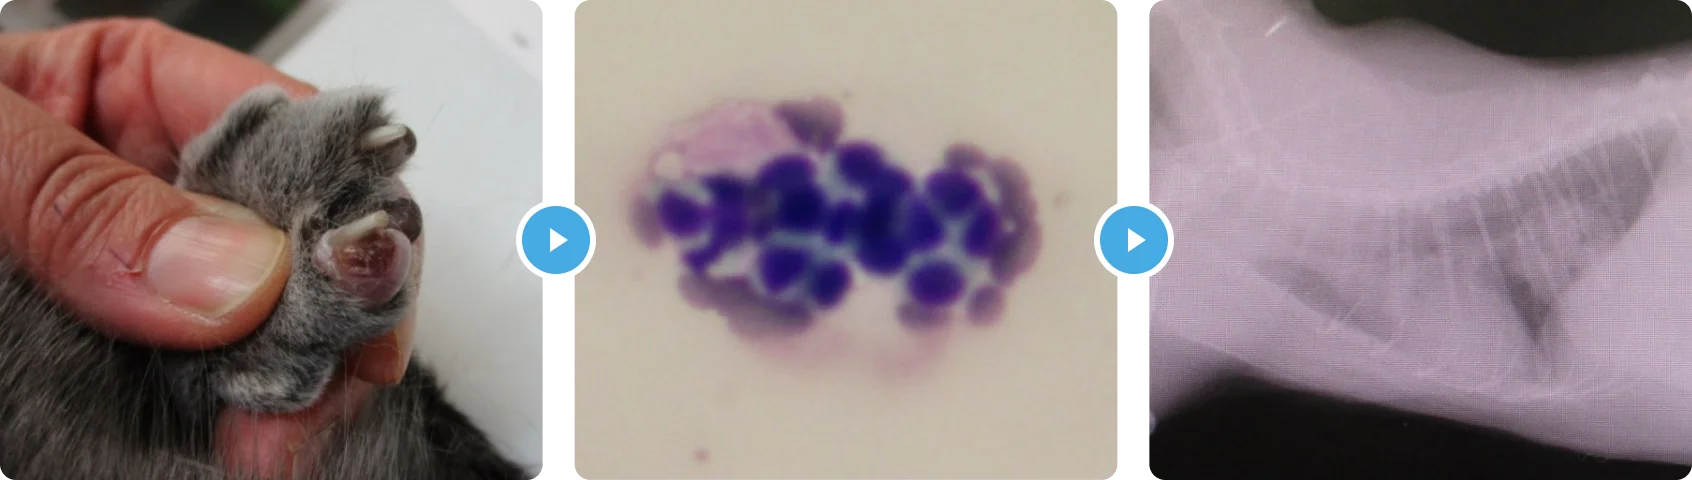

はいがん(はいししょうこうぐん) 肺癌(肺指症候群)

- 症状の説明

- 治療の内容

身体検査からは左前肢の爪に出血があり、爪の根元が腫れていました。その他、本人には症状がなく元気とのことでした。ただ爪をみると単なる外傷でなく見えたので、爪先の細胞診検査とレントゲンを撮りました。

その結果、爪の根元からはやや異型性のある上皮性系の細胞が採取され、肺には腫瘤がみられました。以上の所見より、「肺癌の爪先転移による跛行」と診断しました。

未分化な腫瘍細胞は血流にのり、指先でつまるのかそこに転移病変を作ることがあります。肺指症候群といわれ、予後の悪い肺癌といわれています。残念ながら、治すことは難しいため、痛みの緩和と苦しくなったら酸素吸入での対処をしていきました。